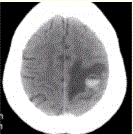

问题 患者女,55岁,右侧肢体无力3d。头颅CT显示如下图。 下一步治疗应首选(提示1周后,患者右侧肢体瘫痪,复查CT如下图。)

选项 A.手术切除 B.继续保守治疗 C.放疗 D.化疗 E.激素治疗 F.抗炎治疗

答案 A